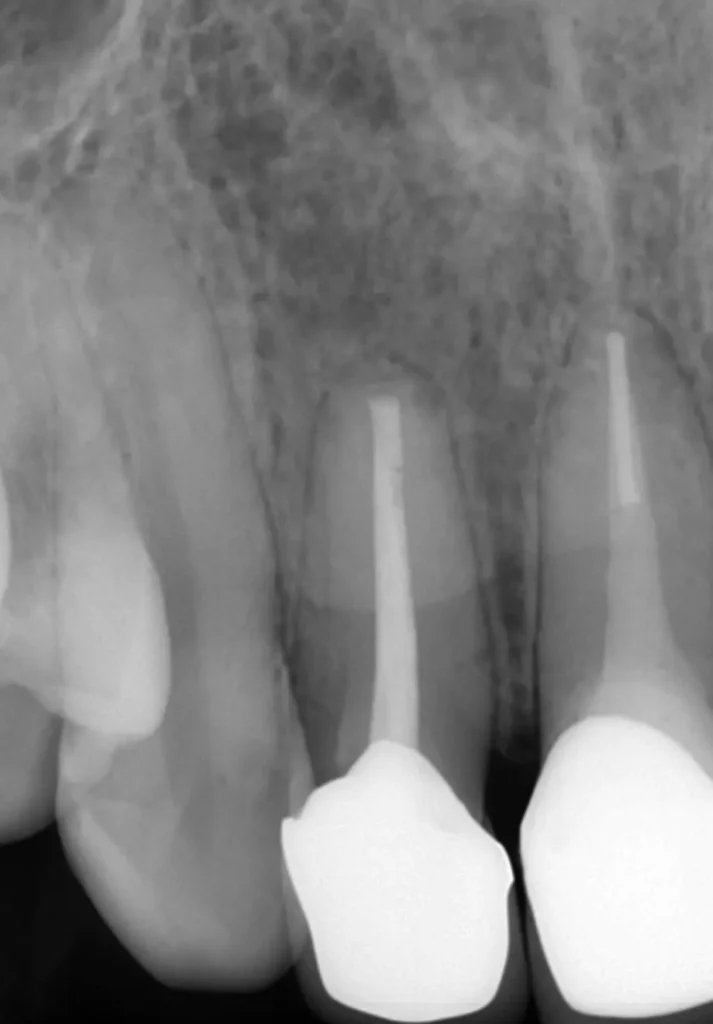

初診時レントゲン写真

インプラント隣の歯の根の先に人工材料が逸出しています。

初診時レントゲン写真2

右側(向かって左)の歯は以前、他院で外科的歯内療法を受けています

術中レントゲン写真

右側1番(真ん中)の歯は歯根破折のため抜歯になりました(コツ補填材を抜歯窩に充填)

2本とも歯根端切除術を行いました